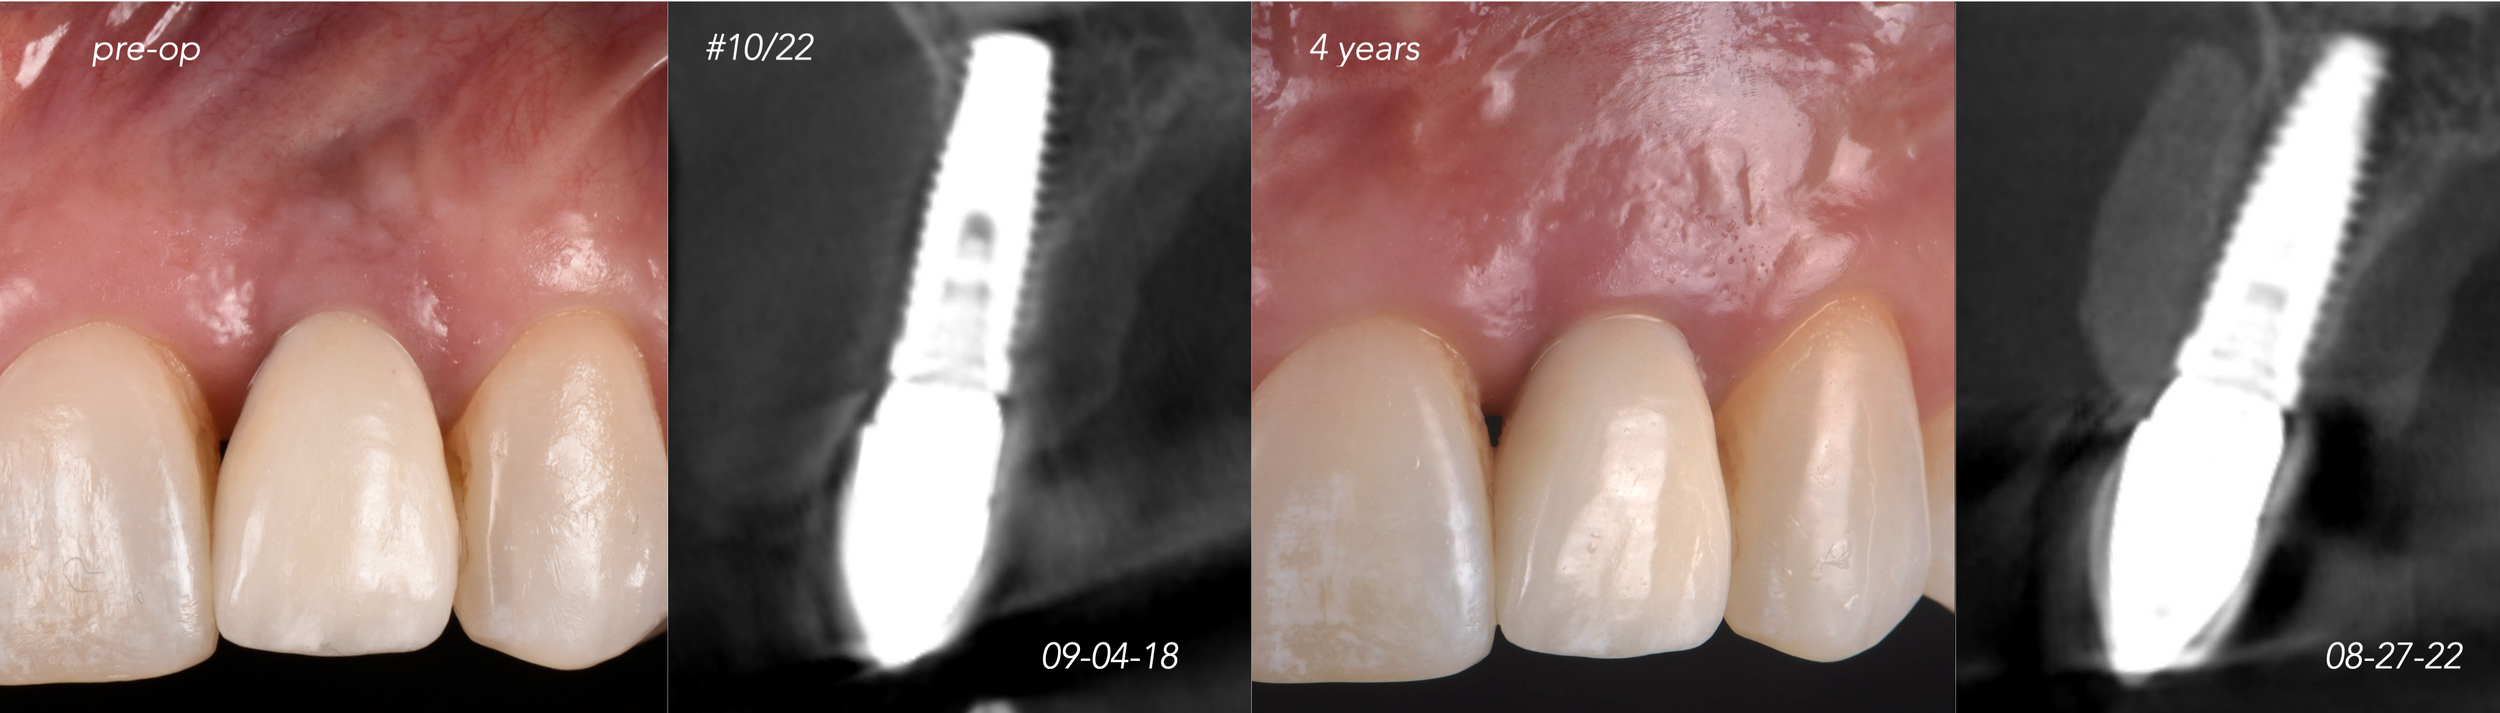

CASE 5. IMPLANT BONE DEHISCENCE